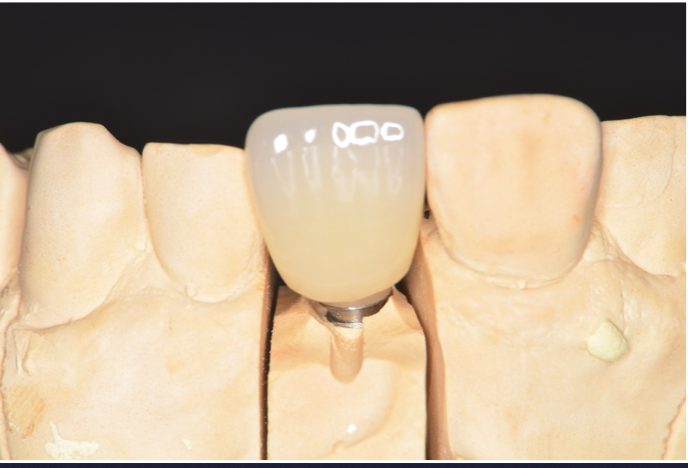

骨が十分に無いところに、骨造成を行いインプラントを埋入した一症例です。前歯なので審美もこだわりながら治療しました。

骨が十分に無いところに、骨造成を行いインプラントを埋入した一症例です。前歯なので審美もこだわりながら治療しました。